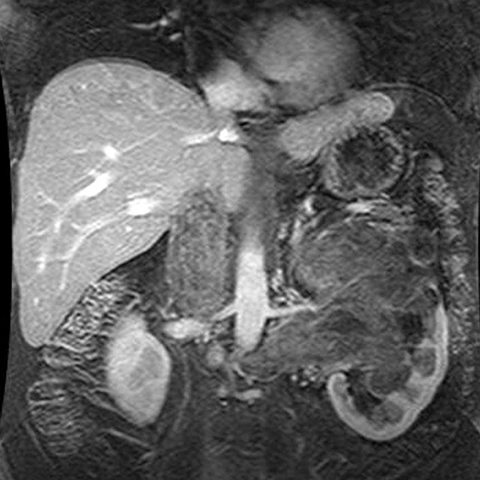

67-year-old male with flank mass and hematuria [2 of 3]